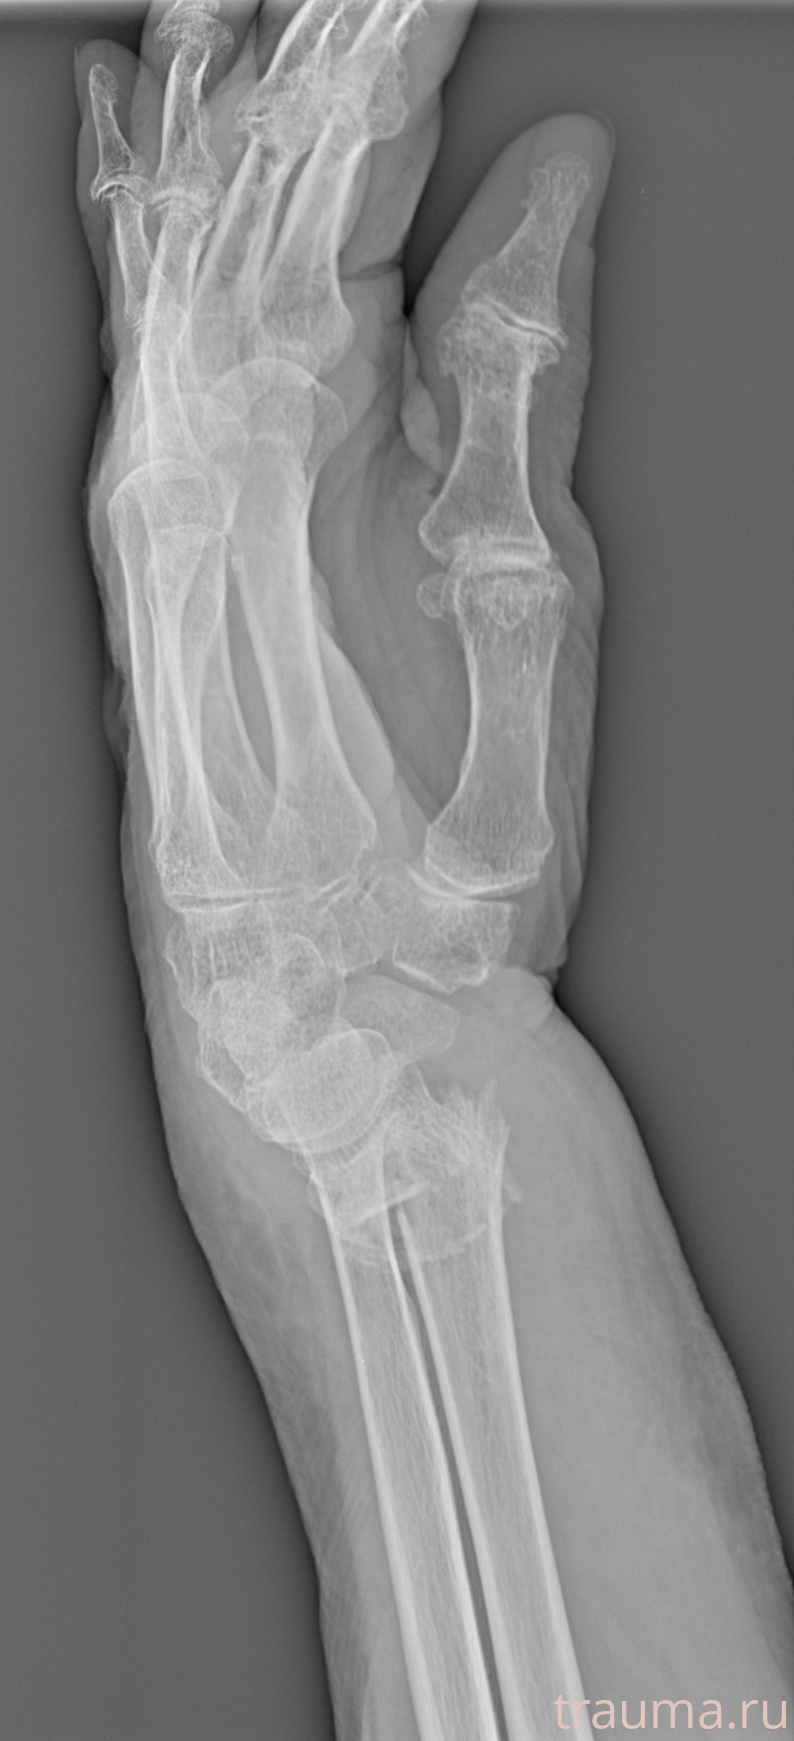

Рентгенограммы

Рентген на дому: по вашему адресу приезжает врач-рентгенолог, травматолог-ортопед с мобильным рентгеновским аппаратом, проводит диагностику травмы или заболевания, делает необходимые рентгенограммы, дает рекомендации по дальнейшему лечению. Получить качественные снимки в домашних условиях возможно благодаря уникальной методике, разработанной МосРентген Центром для института  Склифосовского